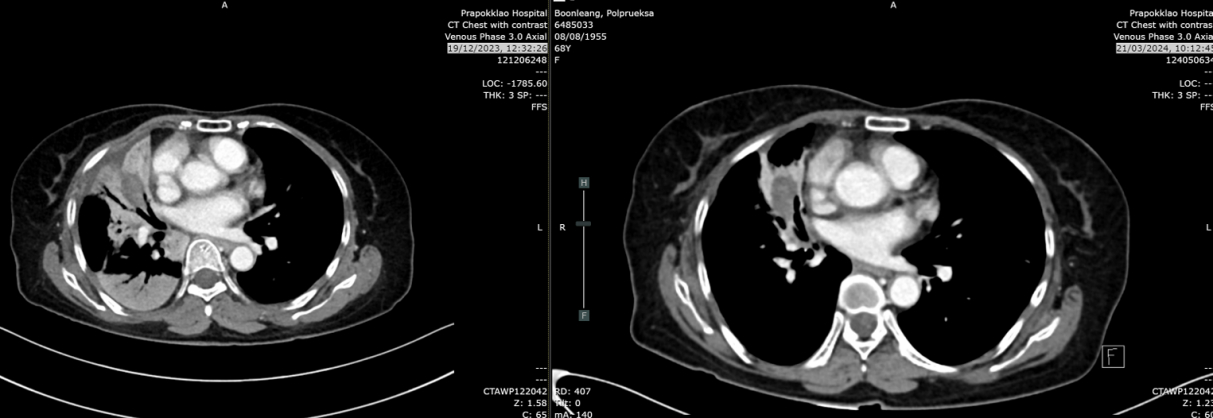

复查CT(2023-12-19):CT示肿块轻度增大至4.1cm(较7月增长24%),右肺上、中、下叶新见牵拉性支气管扩张及实变影,鉴别诊断包括浸润性转移、感染或混合性肺不张/实变。无肝、肾上腺、淋巴结或骨转移。

2024年3月21日:肿块缩小至2.8cm,实变及结节较前减少,考虑肺转移灶部分消退。

2024年6月17日:肿块略增至2.9cm,亚厘米级淋巴结。

2025年8月26日:肿块2.2cm,右肺上叶、中叶结节0.3-0.4cm稳定,中叶新增磨玻璃影(考虑感染或炎症),无新增转移灶。

疗效总结:自治疗开始计算,无进展生存期(PFS)达186周(3.5年);自停药后计算,PFS为102周(2年)。